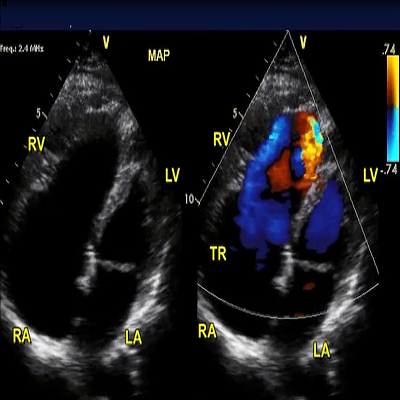

Rheumatic mitral stenosis

Rheumatic mitral stenosis